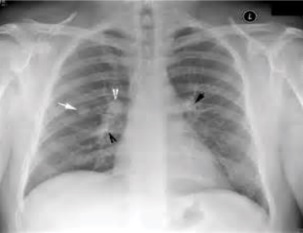

Not all nodules are “solitary pulmonary nodules.” There might be multiple nodules.This image shows multiple lung nodules (indicated by the black and white arrows), which were caused by tuberculosis infection: